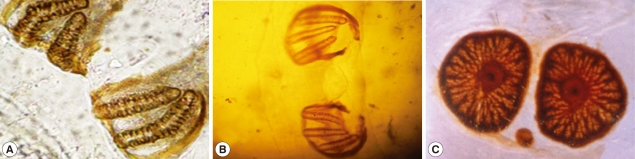

The second stage larvae of Sarcophaga species were conical in shape and creamy white in color, and measured 13-14 mm in length and about 3 mm in width (Fig. 1A). The third stage lar-vae of Sarcophaga species were different from the second stage larvae in the sense that they were grayish in color and measured 18-19 mm in length and about 4 mm in width (Fig. 1B). The third stage larvae of Oestrus species were dark brown in color, spindle in shape, and segmented. They measured 20-21 mm in length and about 6 mm in width. The dorsal surface was convex and smooth, while the ventral surface was spiny (Fig. 1C). The body of all types of larvae was pointed anteriorly and progressively widened posteriorly.

Light microscopic findings

The second stage larvae of Sarcophaga species closely resembled those of the third stage larvae with the exception of posterior spiracles.The larvae were subcylindrical in cross-sections with a flattened ventral surface, truncated posteriorly, and tapering toward the anterior extremity. The posterior end was narrowed with a pit-like depression, where the posterior spiracles are located. It ends with prominent bifid anal swellings or cerci. Body segments were banded with transverse spinous swellings. The anterior end was attenuated and had a pair of projecting papillae. Extending from the lateral surfaces of the second segment, the anterior spiracles were small and fan-like structures carrying from 7-10 branches and each branch ending with a round spiracle as shown in Fig. 2.

The posterior surface of the anal segment had a distinct cavity, and contained posterior spiracles which are a characteristic feature for differentiation as shown in Fig. 3. In the second stage larvae of Sarcophaga species, the posterior spiracles consisted of 2 elongate slits each surrounded by an incomplete sclerotized peritreme. In the third stage larvae of Sarcophaga species, the posterior spiracles are located near each other and each plat was formed of widely opened peritreme with a very indistinct button (Fig. 3A). Each plate contained of 3 elongate slits. The median one was straight, while the lateral ones were curved anteriorly (Fig. 3B). In Oestrus species, each plate of the posterior spiracles was surrounded by a complete sclerotized peritreme (Fig. 3C). Its slits were indistinct in the form of several small pores and a centrally located button.

Fig. 1

Macroscopic examination of the 3 different types of larvae. The second stage larvae of Sarcophaga sp. (A), the third stage larvae of Sarcophaga sp. (B), and the third stage larvae of Oestrus sp. (C).

Fig. 2

Anterior respiratory spiracles. These are small and fan-like structures carrying from 7-10 branches.

Fig. 3

Posterior respiratory spiracles. In the second stage larvae of Sarcophaga sp., the post spiracles consist of 2 elongate slits (A). In the third stage larvae of Sarcophaga sp., the post spiracles have 3 elongate slits (B). In Oestrus sp., its slits are indistinct in the form of several small pores and centrally located button.